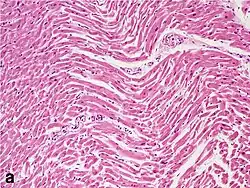

Under the microscope, myocardial infarction presents as a circumscribed area of ischemic, coagulative necrosis (cell death). On gross examination, the infarct is not identifiable within the first 12 hours.[22]

Although earlier changes can be discerned using electron microscopy, one of the earliest changes under a normal microscope are so-called wavy fibers.[23] Subsequently, the myocyte cytoplasm becomes more eosinophilic (pink) and the cells lose their transversal striations, with typical changes and eventually loss of the cell nucleus.[24] The interstitium at the margin of the infarcted area is initially infiltrated with neutrophils, then with lymphocytes and macrophages, who phagocytose ("eat") the myocyte debris. The necrotic area is surrounded and progressively invaded by granulation tissue, which will replace the infarct with a fibrous (collagenous) scar (which are typical steps in wound healing). The interstitial space (the space between cells outside of blood vessels) may be infiltrated with red blood cells.[22]

| Myocardial histologic parameters (HE staining)[26] | Earliest manifestation[26] | Full development[26] | Decrease/disappearance[26] | Image |

| Stretched/wavy fibres | 1–2 h |